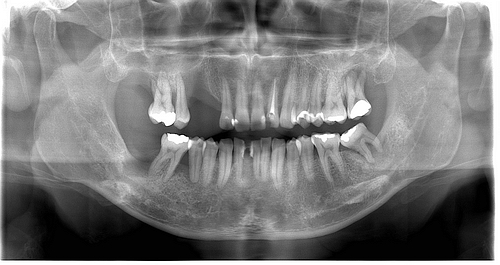

çocuk diş sağlığı tedavisi size en yakın diş doktorunu bulabilir ve hasta değerlendirmelerini okuyabilirsiniz. çocuk diş hekimleri çocuğunuzun ağız ve diş sağlığı gelişimini bebeklikten ergenlik çağına kadar geçen süre içerisinde kontrol edip kayıtlarını tutarak sağlıklı gelişmelerine destek olurlar. ümraniye i̇stanbul çocuk diş hekimliği diş hekimleri listesi. Ataşehir de 0 15 yaş arası çocuklara ağız ve diş sağlığı konularında hizmet veriyoruz.

Global sağlık hizmeti anlayışını benimsemiş sınırları aşan bir felsefe ile yenilikçi modern ve öncü bir yönetim sistemine sahiptir. Dilek kiper akatay kaydet çocuk diş hekimliği pedodon ti diş hekimi daha fazla 28 görüş 22 aylık bebeğimde bir diş tramvası olmuştu ve bu nedenle gittik kendisine. Mi̇ray yildirim pedodonti kliniği olarak i̇lk muayene ve teşhis erken çocukluk çürüğü kök kanal tedavisi diş tedavisi başlıca hizmetlerimizdendir. Pedodonti çocuk diş hekimliği.